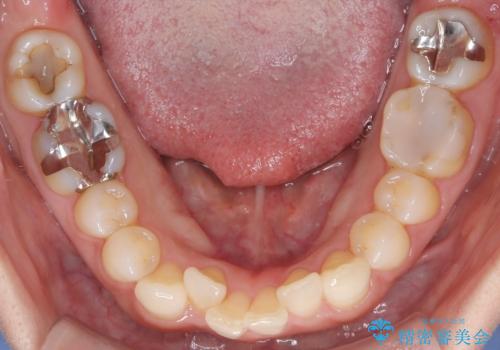

- 「八重歯をきれいにしたい」とのご希望で来院されました。診察の結果、上顎犬歯の萌出スペースが不足しており、典型的な八重歯(叢生)の状態でした。上下の歯の中心(正中)のずれや、奥歯のかみ合わせ(臼歯関係)のアンバランスも見られたため、単に見た目を整えるだけでなく、全体的な機能改善も必要と診断しました。

初期段階では、リンガルアーチを上顎に装着し、奥歯を少しずつ後方へ移動させていきました。これにより前歯部の歯列に十分なスペースを確保。その後、マルチブラケット(ワイヤー矯正)を用いて、突出した八重歯を正しい位置に誘導しながら、歯並び全体を整えていきました。